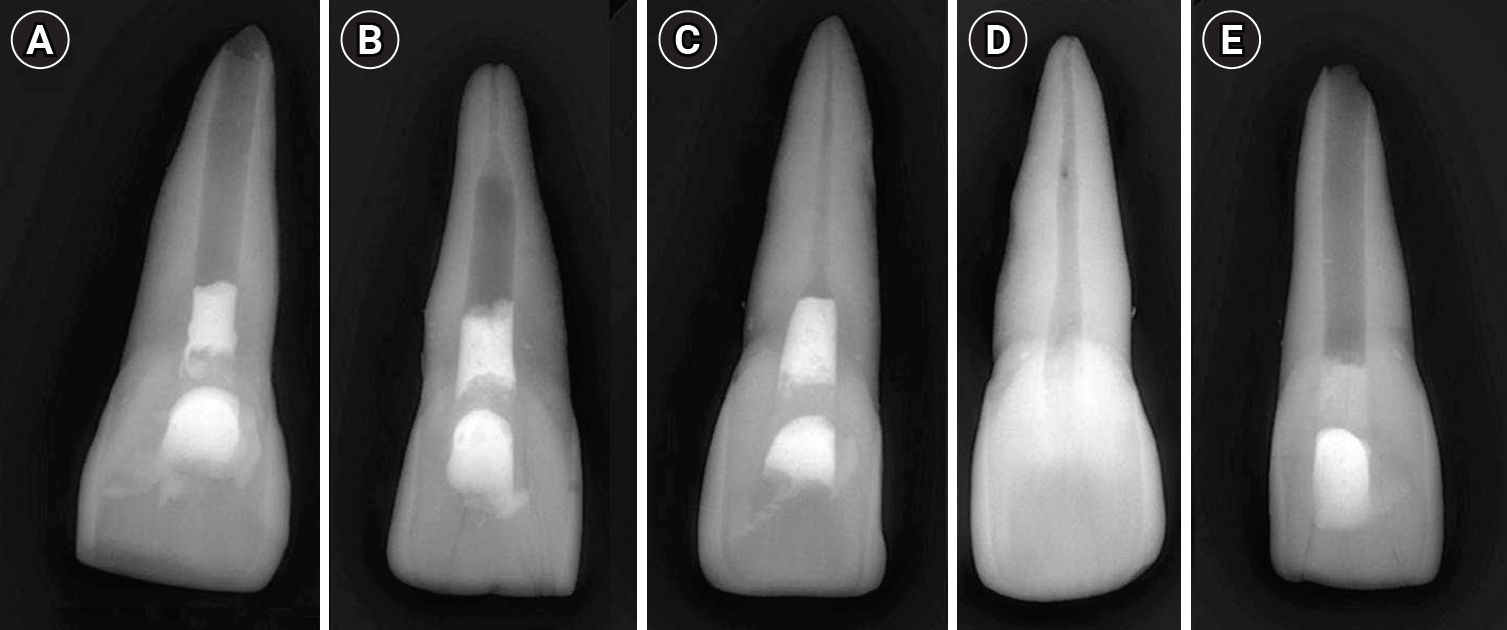

Fracture resistance

Descriptive statistics for mean load (N), fracture resistance (MPa), and coefficient of variation (CV%) are presented in Table 1. The Kruskal-Wallis test revealed significant differences among the groups (H(4) = 20.270, p < 0.05). Post hoc pairwise comparisons using Bonferroni-adjusted Dunn’s tests showed that the negative control (Group D) exhibited significantly higher fracture resistance than Groups A (p < 0.05), B (p < 0.05), and E (p < 0.05). No statistically significant differences were detected among the experimental groups (A–C) or between Group C and the negative control (Group D).

Group C displayed the highest mean fracture resistance among the experimental groups (5,019.05 ± 4,968.58 MPa) and was comparable to the negative control (15,513.33 ± 13,244.33 MPa). However, this observation should be interpreted cautiously, as differences among the experimental groups were not statistically significant (p > 0.05).

Load at failure

Mean load values per cycle also varied significantly among groups (H(4) = 20.332, p < 0.05). Group D (573.33 ± 186.96 N) had significantly higher load capacity compared with Groups A (377.5 ± 105.72 N, p < 0.05), B (362.5 ± 153.79 N, p < 0.05), and E (316.67 ± 109.65 N, p < 0.05). No significant differences were found between Groups A, B, and C.

Number of cycles to fracture

The number of cycles to failure did not differ significantly among groups (H(4) = 5.468, p > 0.05). The highest mean number of cycles was recorded for the negative control (2,972.33 ± 3,334.44), followed by Group C (821.50 ± 893.79). The lowest values were observed in the positive control (514.33 ± 549.95).

The distribution of mechanical parameters among the experimental groups is illustrated in Figure 2. Boxplots show the variability in load at failure (Figure 2A), fracture resistance (Figure 2B), and number of cycles to fracture (Figure 2C) across all five groups.

Figure 2.

Boxplot representation of mechanical performance across experimental groups. Boxplots illustrate the distribution of (A) number of cycles, (B) cycle number to failure, and (C) load at fracture (N) for the five experimental groups: completely immature, apical closure, apical closure with wall thickening, negative control, and positive control. The boxes represent the interquartile range (IQR), with horizontal lines indicating the median values. Whiskers denote 1.5 × IQR, and outliers are shown as individual points.